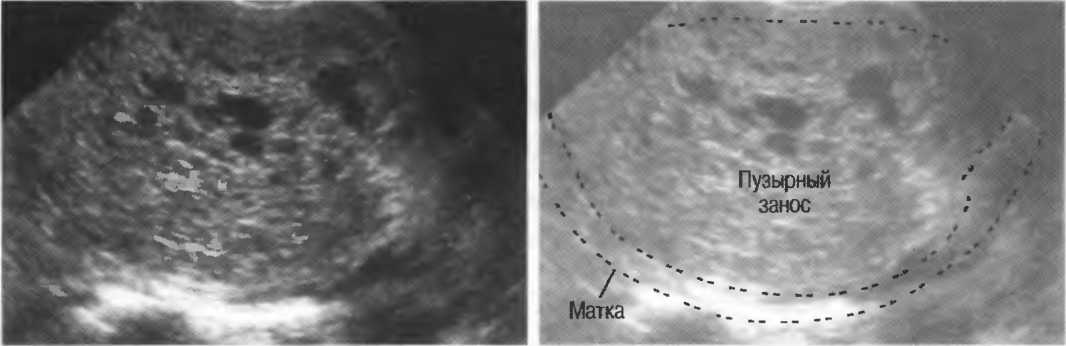

Медицина и диагностика: Инвазивный пузырный занос на УЗИ